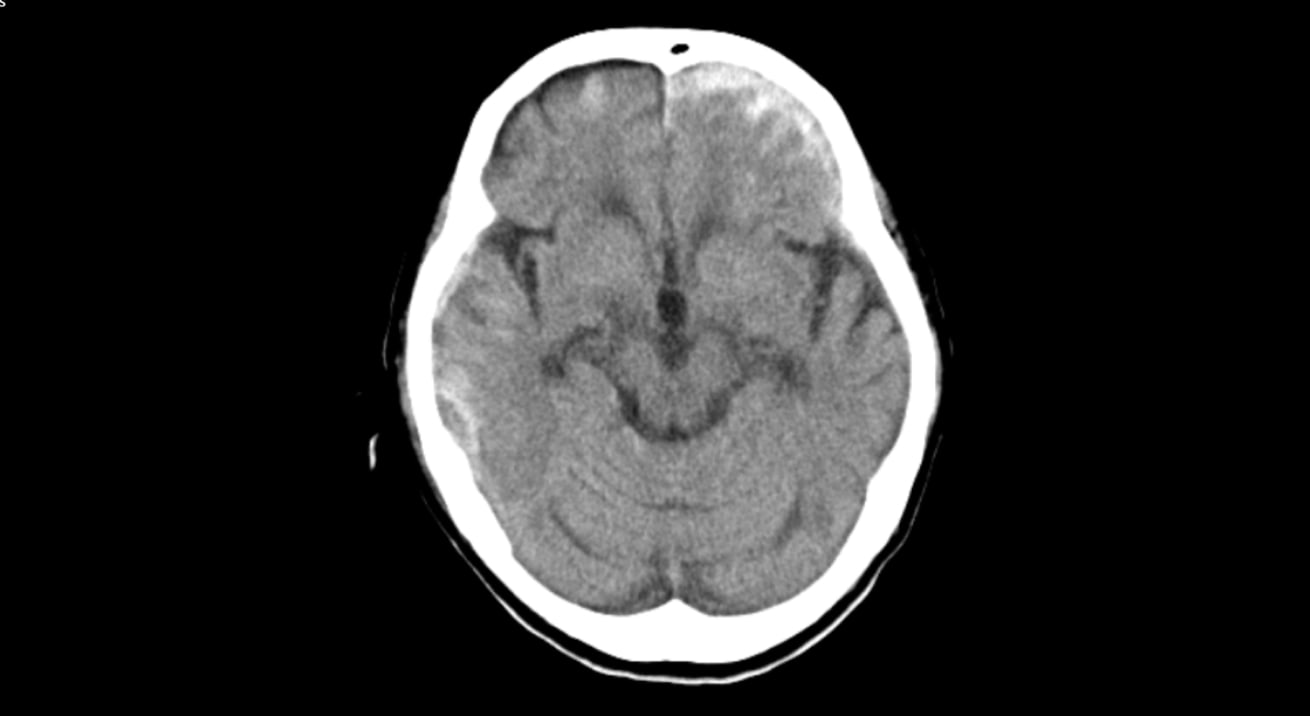

- CT画像情報から頭蓋内の高吸収・低吸収領域を抽出

頭部単純CTの画像情報から頭蓋内の高吸収・低吸収領域を抽出し強調表示をします

- 頭部単純CTの画像情報から頭蓋内の高吸収・低吸収領域を抽出し強調表示をします

- 頭蓋内で前後のスライス及び同一スライス内の左右で比較して組織構造もしくは組織境界の不明瞭化が見られる領域を表示します

- 抽出領域がセグメンテーション表示されることで視覚的な確認が可能です